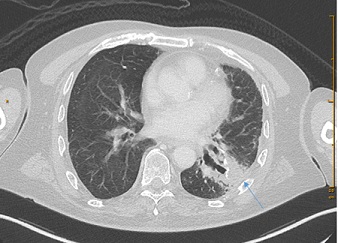

In 2017, in the lower lobe of  the left lung metastasis was found, the biggest one was about 11 mm in diameter (Figure 5). CA 19-9 was 404 kU/l (Figure 2). The combination a wedge resection and RFA was choosen as treatment and performed in October 2017. KRAS p. Gly12Arg and TP53 p.Arg306Ter tumor mutations were found after retrospective molecular diagnostics. 50 Gy (25 fractions a 2 Gy) radiotherapy of the thorax was also performed in 2018 as well as addivive chemotherapy with gemcitabine and capecitabine (6 cycles) from November 2017 until April 2018 and followed by GEM and capecitabine (4 cycles) from October 2018 until January 2019. Regular follow-up with tumor marker CA 19-9 showed once more a significant increase in January 2022 (form 31.4 kU/l up 167 kU/l in a year period of time) (Figure 2). In MR check up, a suspicious solid component was found in the lower lobe of the left lung (Figure 6), a biopsy was performed in Februar 2022. The histopatology showed fibrotic tissue without metastasis. At present the patient is doing well and is recurrence free. In his life the patient had some additional surgeries such as a radical prostatovesiculectomy due to adenocarcinoma Gleason-Score 6 (1998), epididymectomy (2014), osteoma resection frontal (1990, 2006), a benign tumor resection from left shoulder (2004), osteonecrosis resection right knee (1995) and lipomectomy on the neck (2016).

Figure 5: Axial images from a contrast-enchanced CT scans of thorax showing metastasis of a left lung.

Figure 6: Axial image from a contrast-enchanced CT scan of thorax showing a new suspected scar in a left lung after primary operation.